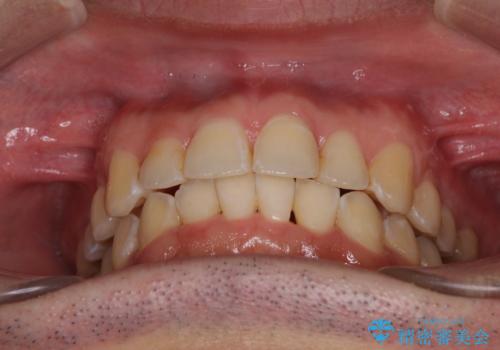

ディープバイトと叢生を解消 インビザライン矯正

ディープバイトが改善されたことで、顎への負担が軽減され、更には上顎前歯の突出感も改善することができました。

矯正治療後には欠けてしまった修復物をセラミックインレーにて修復治療しました。